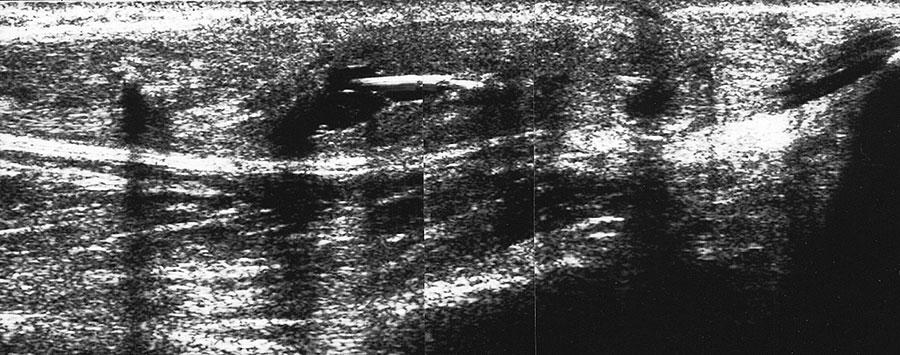

Fibulaverletzung beim Kind

Abgehobenes Periost mit periostalem Hämatom (rechts) mit Gegenseite (links). Die Kortikalis wird unterbrochen von der noch offenen Wachstumsfuge der Fibula.

Abbildung 12

Lagerung: Rückenlage, leichte Innrotation des Fußes.

Schnittebene: LS über distaler Fibula.

Referenzstruktur: Fibula im Längsverlauf.

Befunde: Bei Kindern wird nach Distorsion des OSG mitunter eine Lösung der Fibulafuge vermutet, die jedoch in der klinischen Praxis sehr selten ist. Die seitenvergleichende Untersuchung zeigt dann ein aufgrund des dicken und bei Kindern gut abgrenzbaren echogenen Periosts ein periostales Hämatom, was aber auch ein Hinweis auf eine Fissur oder Fraktur sein kann (Abb.12).